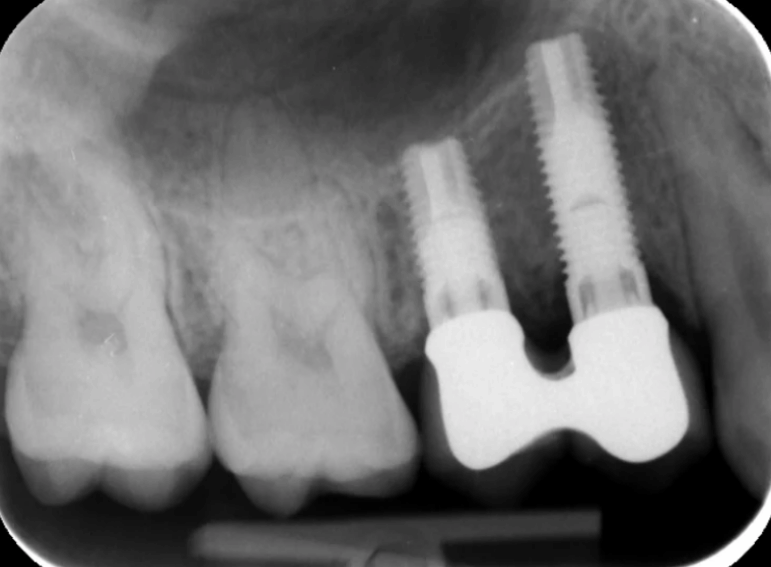

Replacement of retained primary teeth in a patient with hypodontia.